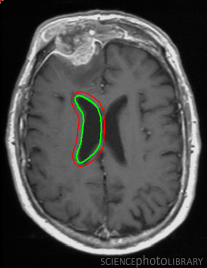

Refer to captionRefer to caption(a)(b)Refer to captionRefer to caption(c)(d)Refer to captionRefer to caption𝑎𝑏Refer to captionRefer to caption𝑐𝑑\begin{array}[]{cc}\includegraphics[width=112.0187pt,height=114.33119pt]{Ultra_init-1.pdf}&\includegraphics[width=112.0187pt,height=114.33119pt]{Ultra_Res-1.pdf}\\ (a)&(b)\\ \includegraphics[width=112.0187pt]{Ultra_init-2.pdf}&\includegraphics[width=112.0187pt]{Ultra_Res-2.pdf}\\ (c)&(d)\end{array}

Figure 13: Segmentation of endocardium in B-mode ultrasound images. (a) and (c) show the initializations provided, (b) and (d) show the converged contours. Image source: (a) was taken from [38] and (c) was taken from [39] .

In Figure 13, we show the results for segmentation of endocardium in B-mode ultrasound images, an imaging modality where shape prior information is popularly[40, 41] used to counter the problem of broken/diffuse boundaries between the region of interest and its background. In Figure 14, we show an example where the template based formulation is able to overcome partial loss of signal due to occlusion and still segment the object reliably. We observe that, by incorporating prior knowledge of the shape, we can segment images with partial loss of structure and broken boundaries.